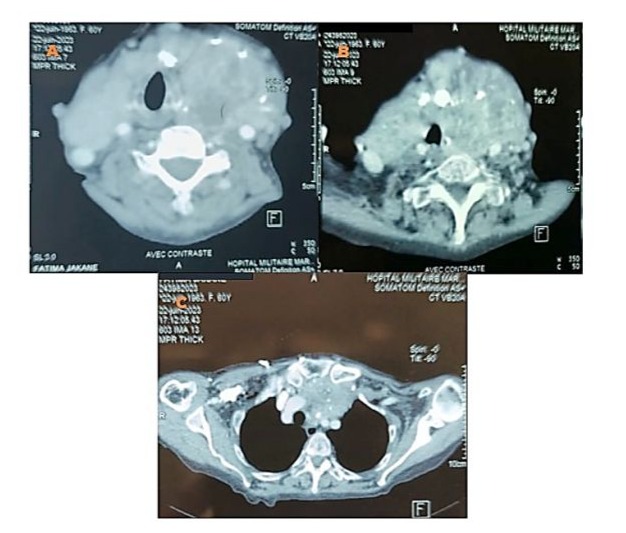

We report the case of a 70-year-old female patient with a history of poorly controlled arterial hypertension, presenting with two coexisting conditions that required either a two-step approach or simultaneous management, involving a thyroidectomy followed by cardiac surgery under cardiopulmonary bypass (CPB). In our case, a simultaneous approach was chosen following a multidisciplinary consultation. With a medical history of poorly controlled arterial hypertension, a multinodular plunging goiter in hyperthyroidism treated with carbimazole 10 mg/day, and atrial fibrillation associated to severe aortic valve stenosis managed with acenocoumarin 4 mg (¼ tablet/day) and bisoprolol 2.5 mg/day, the patient presented with a progressively worsening condition. The onset of her symptom’s dates back to five months prior, marked by a brief episode of syncope, prompting an emergency consultation. Initial evaluation revealed tachycardia due to atrial fibrillation on a background of severe aortic valve stenosis. She was placed on symptomatic treatment. The course of her illness was characterized by a worsening baseline dyspnea, progressing from NYHA class II to class III, accompanied by exertional palpitations without chest pain. The patient was referred to the ENT consultation for progressively worsening dyspnea, associated with orthopnea and a massive goiter, and cardiology consultation for the evaluation of her heart disease. During her recent assessment she also reported reduced exercise tolerance and occasional dizziness with neck symptoms, including subclavicular pain and swallowing limitations. Clinical examination revealed a large goiter deforming the neck, visible on inspection, with signs of tracheal compression. Cardiac auscultation identified an intense systolic ejection murmur at the aortic focus radiating to the carotids, with no signs of right-sided heart failure or peripheral edema. Thyroid ultrasound showed a multinodular goiter containing hypoechoic cystic areas and calcifications, with a plunging thoracic component compressing cervical and superior mediastinal structures. A cervical-thoracic CT scan, with and without contrast injection, confirmed the plunging nature of the goiter. It extended into the anterior mediastinum, displacing the trachea and major vessels without evidence of invasion. The scan revealed a multinodular goiter characterized by generalized thyroid gland enlargement, predominantly affecting the left lobe, with an irregular, lobulated contour. The goiter is characterized by heterogeneity, macrocalcifications, and uneven enhancement, marking hypodense necrotic and/or cystic fluid-filled areas. The large goiter measures 12.13 x 9.06 x 6.63 cm in the left lobe, 10.5 x 6 x 5.36 cm in the right lobe, and 5 cm in the isthmus. It extends upwards to the submandibular spaces and laterally towards the anterior and posterior spinal spaces, particularly on the left side. The jugulo-carotid vascular axes are displaced laterally and posteriorly, but remain unobstructed. The goiter extends downward into the superior level of the anterior mediastinum, filling the prevascular space and pushing vascular structures posteriorly. It reaches the level of the superior border of the aortic arch, coming into contact with the supra-aortic trunks, exerting a mass effect, but without invasion or obstruction. The upper aerodigestive pathways are unobstructed and symmetrical, although there is posterior and rightward displacement at the larynx and trachea level, without narrowing or impact on their lumen, which remains patent and of normal size. (Figure 1) Transthoracic echocardiography revealed severe degenerative aortic stenosis with high pulmonary arterial hypertension for age (PASP through tricuspid regurgitation at 55 mmHg). The left ventricle was non-dilated, hypertrophied with an indexed mass of 107.11 g/m² (eccentric remodeling), end-diastolic diameter (EDD) at 44 mm, end-systolic diameter (ESD) at 28 mm, and preserved systolic function with an ejection fraction (EF) of 55% (biplane Simpson method). (Figure 2)

Figure 1: Axial CT scan with contrast injection showing overall hypertrophy of the thyroid gland, predominantly involving the left lobe, with irregular and nodular contours. The gland exhibits spontaneously heterogeneous density with heterogeneous enhancement (A, B). The upper aerodigestive tract remains unobstructed, with posterior and rightward displacement of the larynx and trachea, whose lumen remains patent and of normal caliber. (A, B) It extends to the superior mediastinum through the thoracic inlet, in a retrosternal position, filling the prevascular space up to the level of the superior border of the aorta and the supra-aortic trunk, which remain patent and uninvolved. (C)